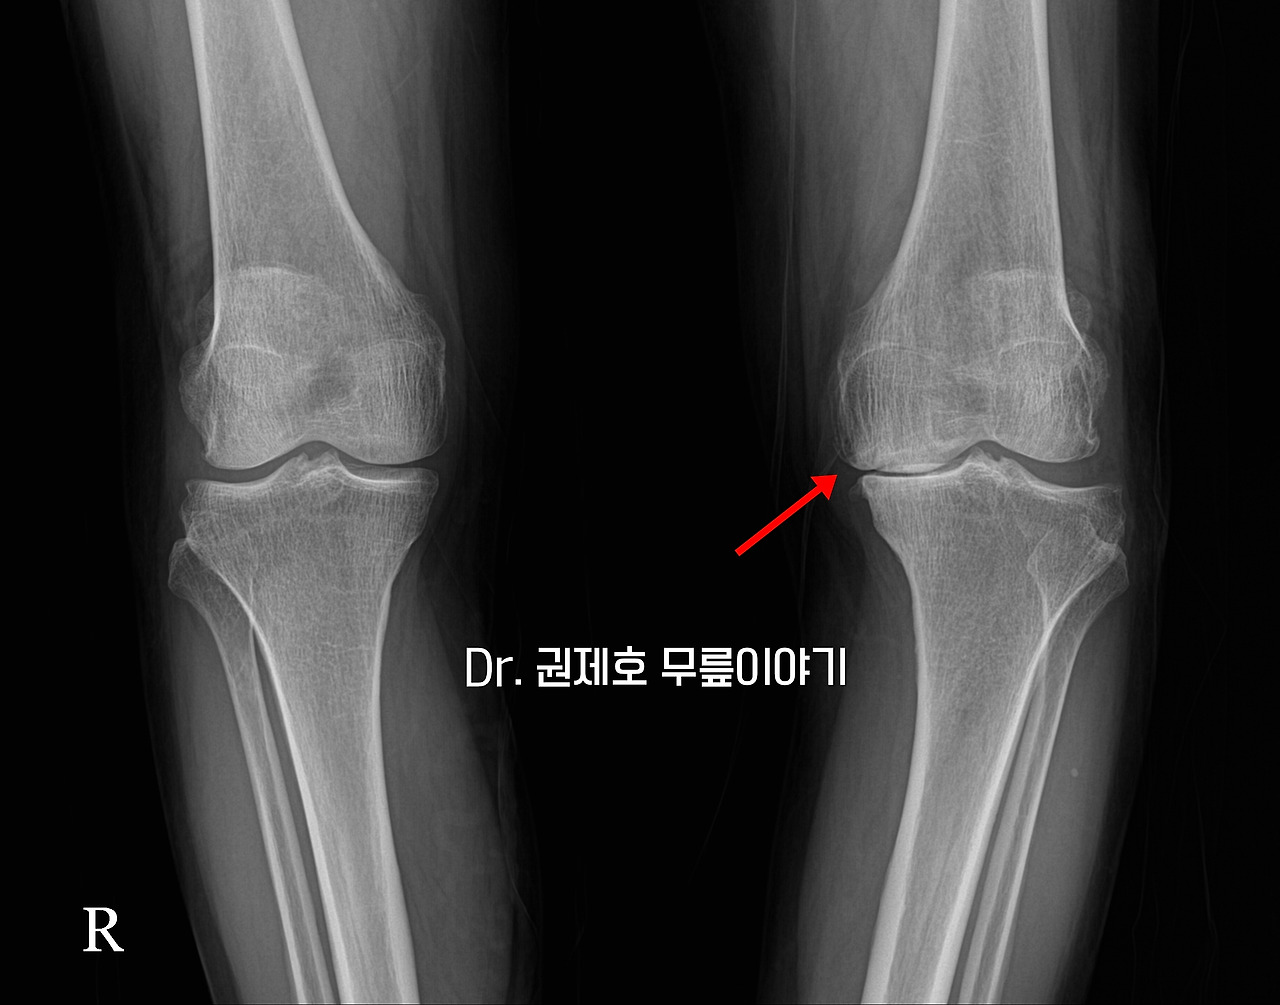

X선 검사를 시행했다. 무릎 차렷 한 상태에서 앞에서 보는 검사이다. 사진에서 보면 왼쪽 무릎에 안쪽 관절 간격이 없어져 붙어버린 소견을 확인할 수 있다.